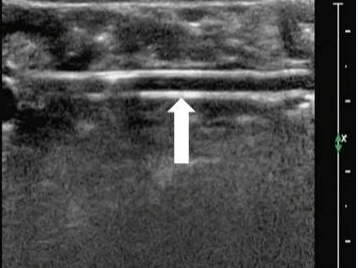

阑尾炎b超图片 诊断书

阑尾炎b超图片 诊断书,

可进行b超检查,准确率可达90-96 6,妊娠期合并急性阑尾炎时,往往其